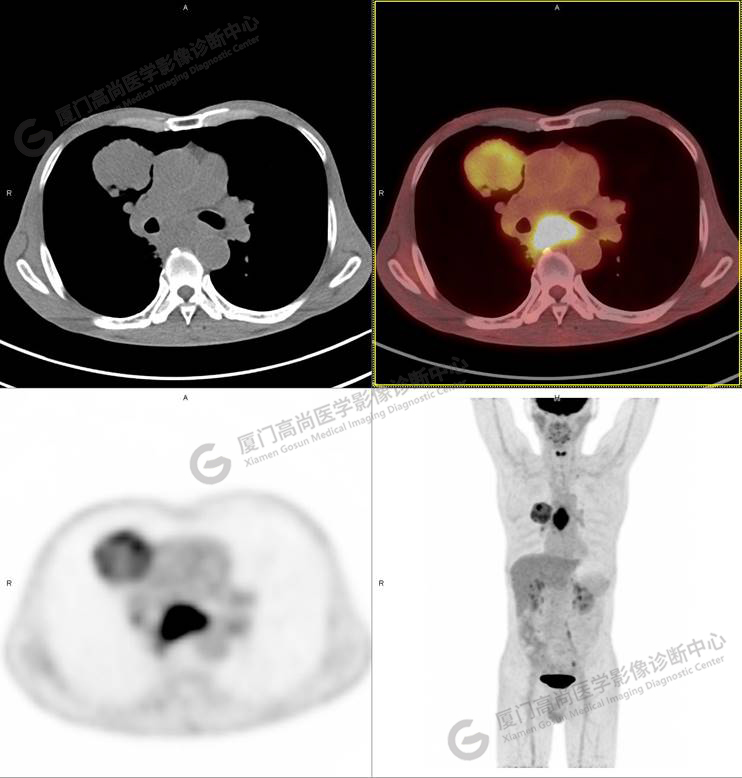

圖1

右肺上葉軟組織密度腫塊,大小約5.9×5.5×6.3cm,形態(tài)不規(guī)則,邊緣見棘突,其內(nèi)密度不均勻,放射性攝取不均勻性增高,SUVmax 6.46;腫塊周圍見多發(fā)小結(jié)節(jié)影,較大者直徑約0.6cm,放射性攝取未見明顯增高。影像學(xué)表現(xiàn)考慮右肺癌并肺內(nèi)轉(zhuǎn)移。

同時發(fā)現(xiàn)食管中段管壁增厚,管腔狹窄,放射性攝取不均勻性增高,SUVmax 9.67。